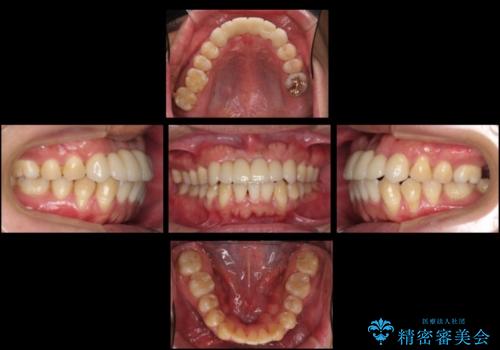

総合歯科治療をやりきったことで、メンテナンスに移行することができました。

左上1番は再根管治療を行いましたが途中で破折が確認されたため、抜歯しています。

また、大臼歯の銀歯もセラミックに全てやりかえています。

左上7番は歯周病によりやむなく抜歯となり、インプラントをおすすめしましたが、希望されませんでした。